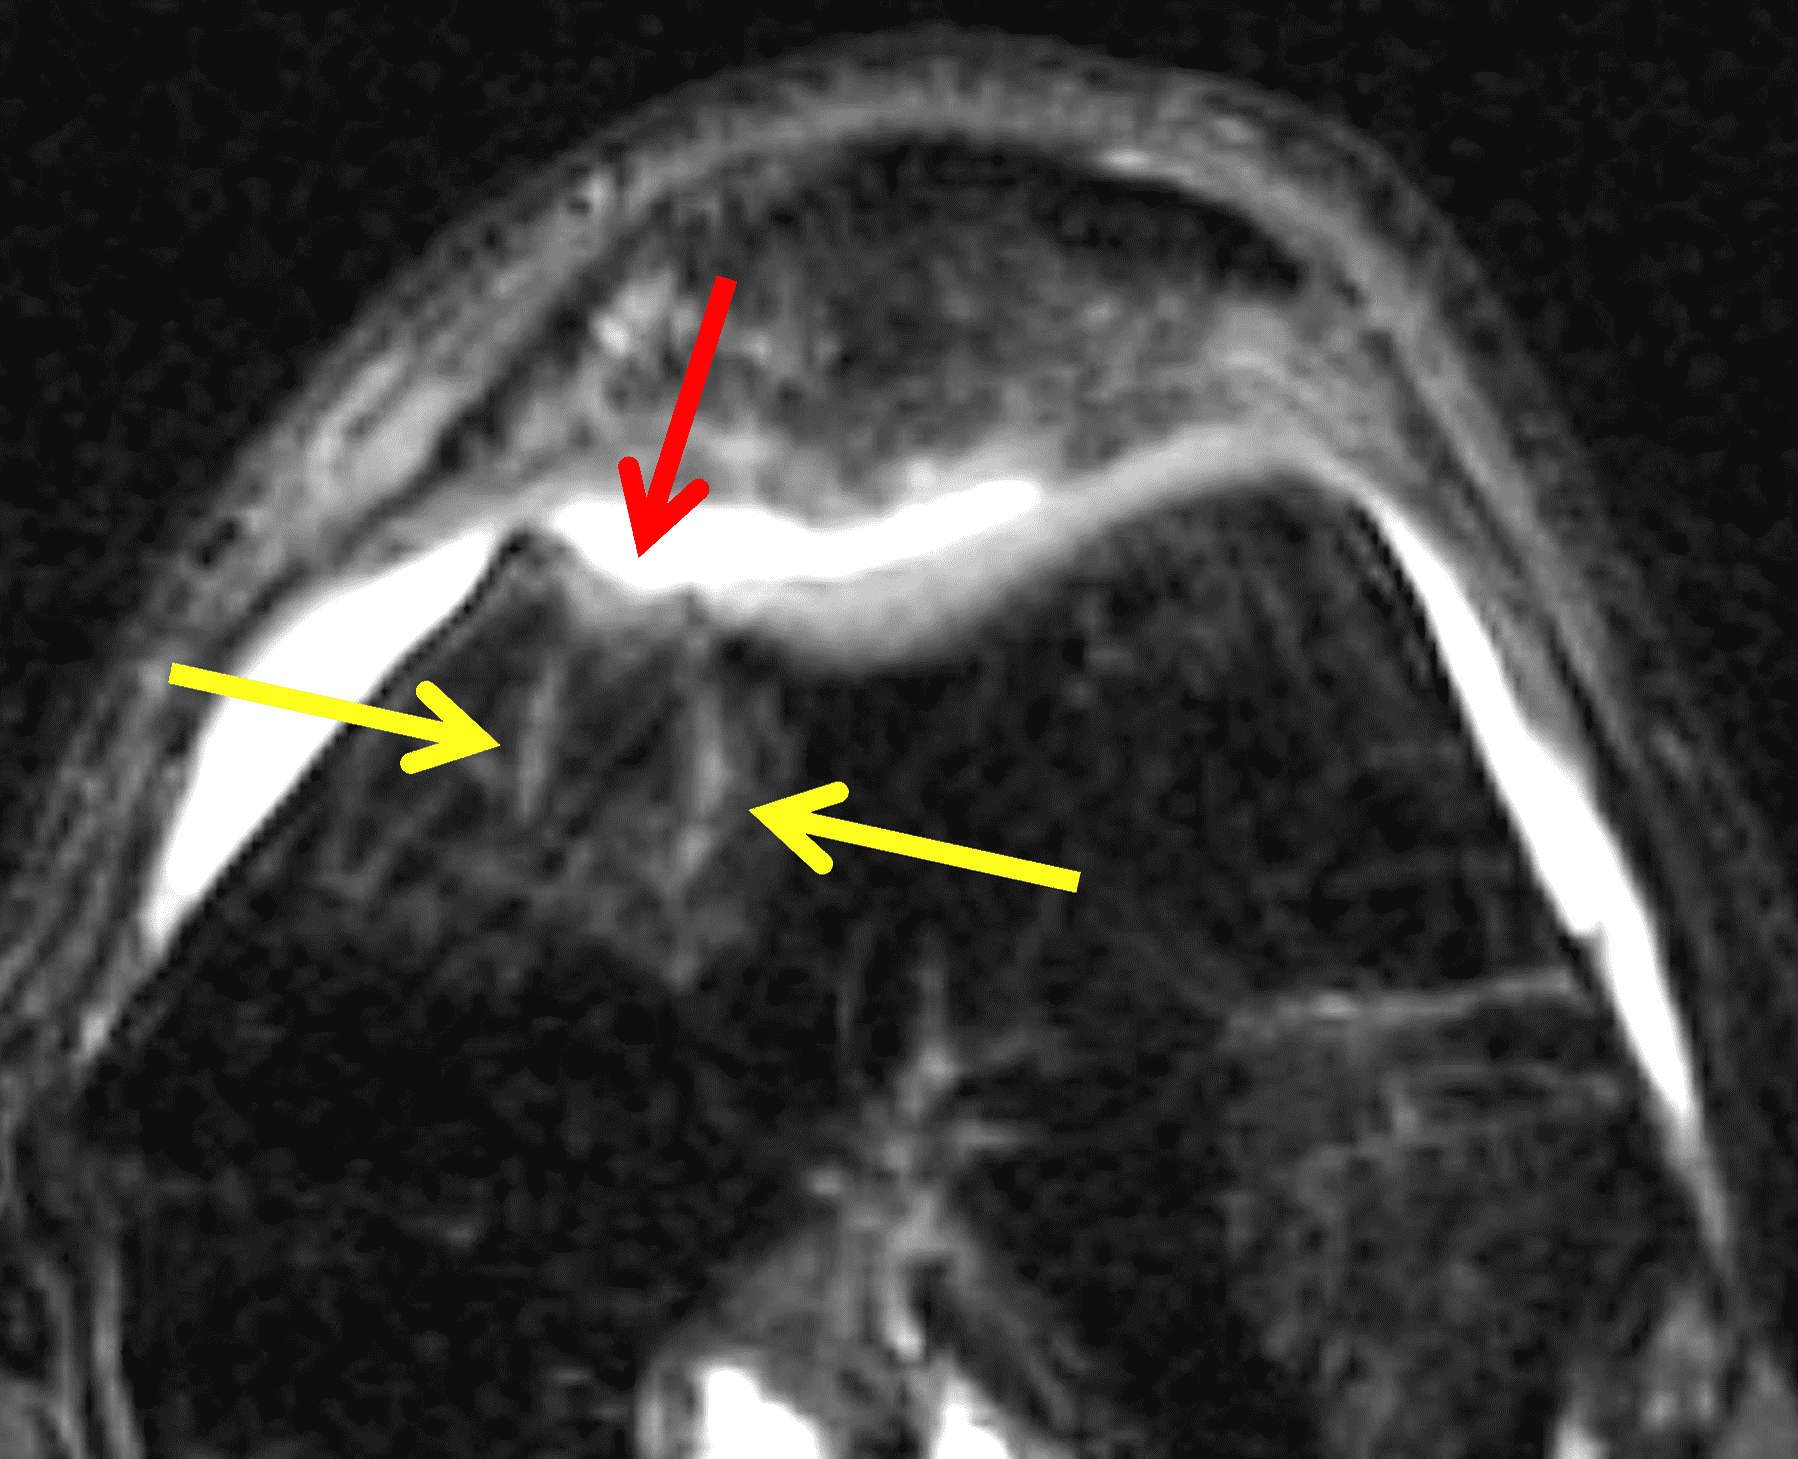

The postoperative imaging appearance of osteochondral allografts is similar to autografts (Figure 2).33 The subchondral bone plate of the donor and recipient sites do not have to match, but the articular surface should be congruent. Grafts that fail to incorporate by one year have a poor prognosis. Persistent marrow edema (beyond 12 months), a thick graft interface containing cysts or fluid, and subsidence of the graft are associated with poor osseous healing and worse outcomes. Extensive host marrow edema and severe synovitis may be a clue to immunologic rejection of the graft (Figure 18).21, 34

Figure 18: Failed osteochondral allograft. (18A) Sagittal fat-suppressed fluid-sensitive image shows the outline of an osteochondral allograft (red arrows) in the medial femoral condyle. Extensive marrow edema in the graft and underlying bone (asterisk) and severe hypertrophic synovitis (yellow arrow) are findings associated with immunologic rejection. (18B) Sagittal CT image acquired to assess graft healing shows lack of osseous integration (black arrows) with mild subsidence of the graft (yellow arrow) within the host site.